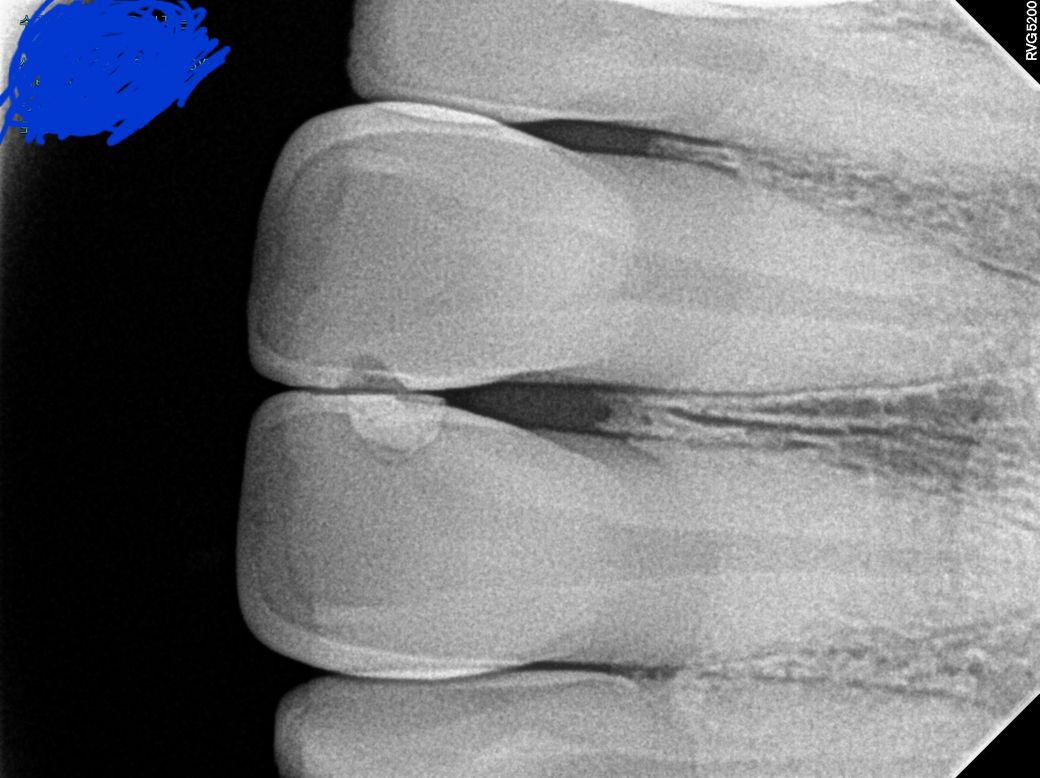

치근단 사진에 보이는 치아 파절처럼 보이는 데 확인부탁드립니다

치근단 사진을 치과에서 받았어요.

앞니 11.21번치아사이를 레진으로 떼운 적 있습니다.

치근단사진은 몇번째 치아인지 정확히 모르는데,

이사진으로 봤을때 치아가 깨진것처럼 보여서 문의드립니다.

• 1번 째 사진

11,21 번 치아 사이에 파절 및 충치가 생겨있는 것 같습니다. 치료 받으러 가시면 됩니다.

1. 큰 사진이 파노라마 방사선 사진이고, 작은 사진이 치근단 사진이며 치근단 방사선 사진상(노란색으로 표시하신 사진 기준) 왼쪽이 11번 치아, 오른쪽이 21번 치아 입니다. 만약 두 치아를 동일한 재료로 떼우신 거라면 11번은 기존 재료가 떨어져 나간 상태로 보입니다.

2. 특별히 파절은 보이지 않습니다. 11,21번 치아의 뿌리끝 1/3 부위를 가로지르는 검은 선은 코의 연조직상이 겹쳐 보이는 것입니다.